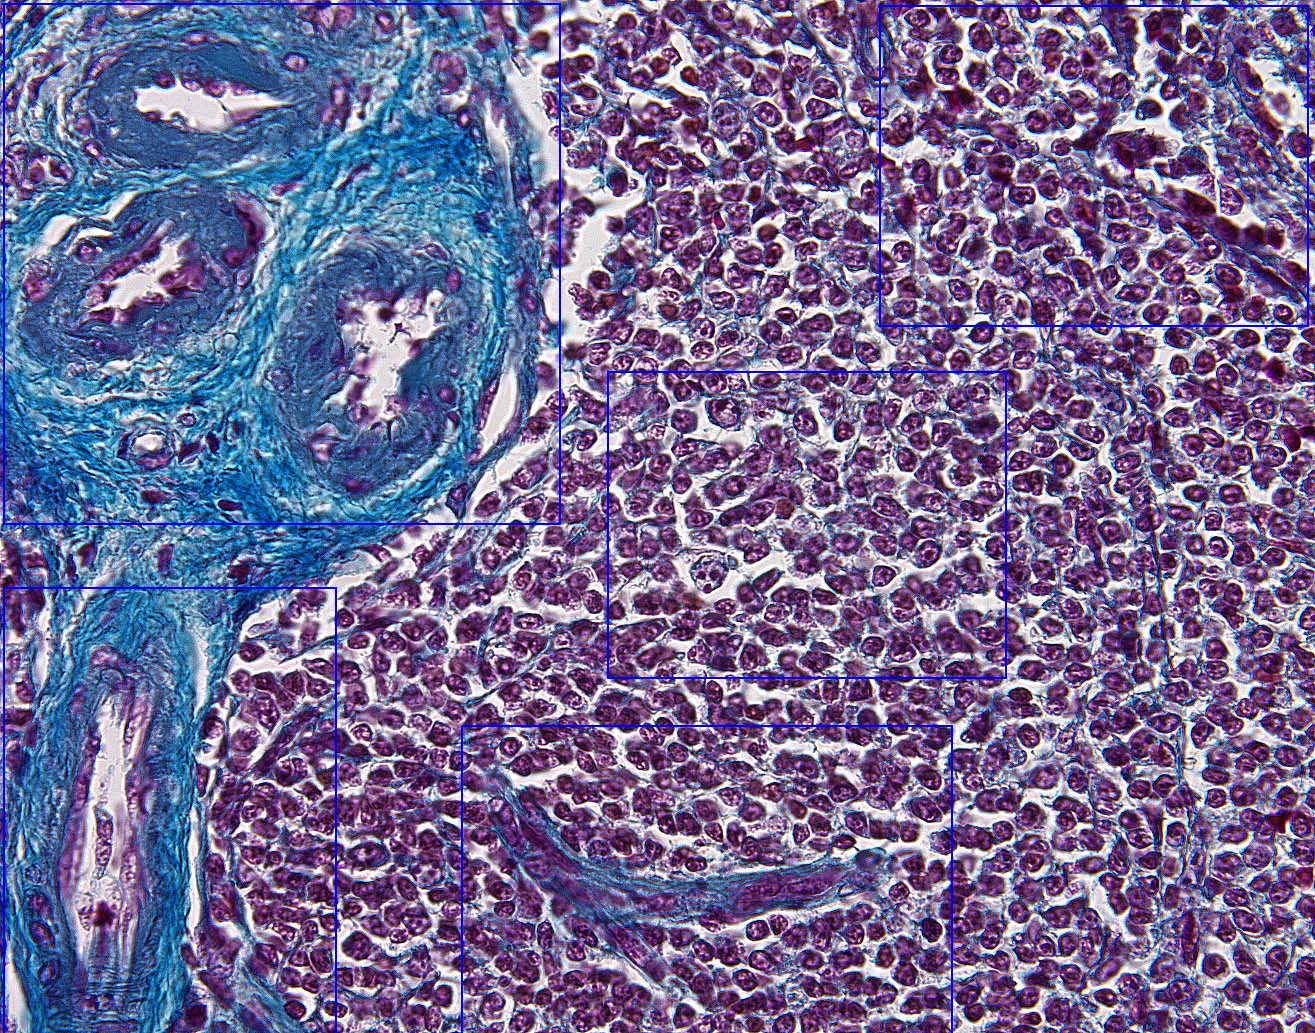

Return To Cartoon of Spleen